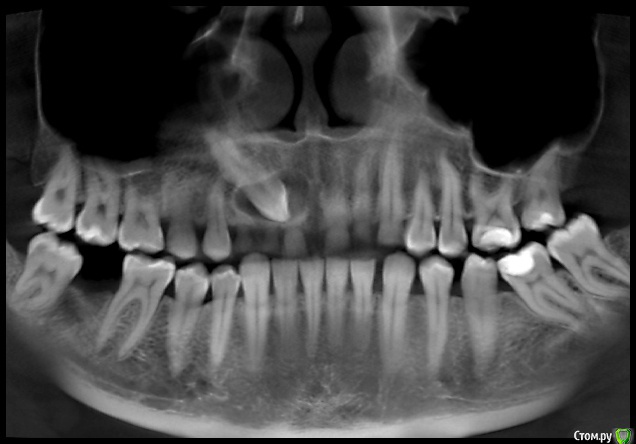

natalie_summerwhile Опубликовано 10 июля, 2017 Автор Поделиться Опубликовано 10 июля, 2017 Во рту вместо клыка молочный Ссылка на комментарий

Qvonti Опубликовано 12 декабря, 2018 Поделиться Опубликовано 12 декабря, 2018 Ортодонтии быть в данном случае!) Ссылка на комментарий